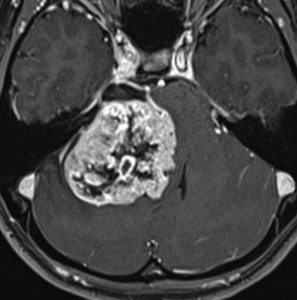

この腫瘍は脳幹部変形がとても強く,大きいので手術摘出するしか選択肢はありません

- 脳幹部の変形が高度な大きな腫瘍になると手術するしかありません

- 4cmを超えると危険だと考えてください

- のう胞性(腫瘍の内部がほとんど液体)のものは4cmを超えても手術は危なくないです

- 巨大な充実性の聴神経腫瘍の手術では命をなくすリスクもあるものです

聴神経腫瘍でまず手術が必要なのは巨大なものです。この4枚の写真は私が実際に手術をした患者さんのものです。脳幹部という脳の最も大切なところが腫瘍によって圧迫されて変形しているのが特徴です。右上のものはのう胞性腫瘍なので大きさの割に手術のリスクは高くありませんが,左上のものは実質性で出血性のものですごくリスクが高い手術でした。左下のものは普通のリスク。右下のものは超高難易度のものです。